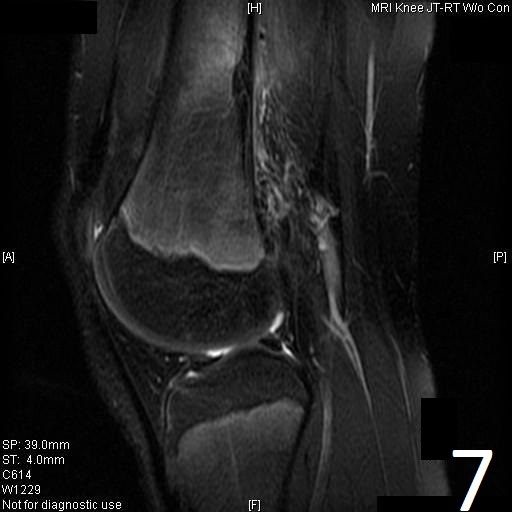

MRI

• Low- signal on T1 (Fig. 8)

• Variable heterogeneneous signal on T2 (Fig. 9).

• Possible extensive hypercellular fibrous tissue and hemosiderin seen on T2

Fig. 6-9: Sagittal T1 (Fig. 6) and T2 (Fig. 7) MRI of the knee demonstrates a fibrous cortical defect. Axial T1W (Fig. 8) and T2W (Fig. 9) show a heterogeneous lesion on distal femur, compatible with nonossifying fibroma.